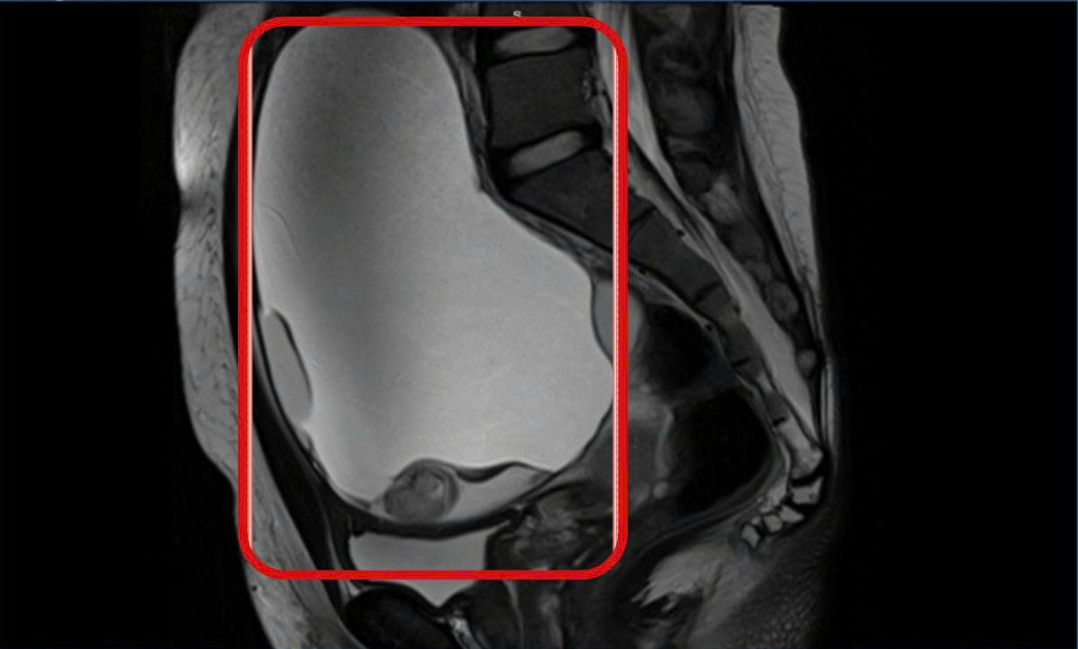

U buồng trứng xoắn - Ảnh BVCC

Ca phẫu thuật được tiến hành khẩn trương. Trong quá trình mổ, ê-kíp phẫu thuật đã bóc trọn hai khối u bì kích thước lớn (15cm và 8cm). Bên trong các khối u chứa nhiều tổ chức như răng, tóc, xương và da đầu, với lượng dịch khoảng 2.000ml. Nhờ can thiệp kịp thời, hai buồng trứng của bệnh nhân được bảo tồn hoàn toàn.